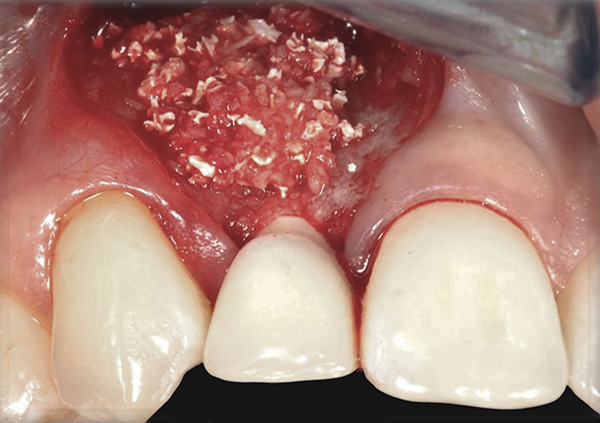

In the esthetic zone it is preferable to avoid elevating papillae because flap elevation may induce recession and create unesthetic black triangles.4 If a flap is necessary to perform a procedure in an edentate area when adjacent teeth are present, the following technique can be used to circumvent blunting papillae. Make a horizontal incision along the midcrestal or palatal aspect of the ridge and terminate the incision 1 mm from the adjacent teeth (Figure 1). The incision is created palatally if it is desired to transpose keratinized tissue to the buccal. From the horizontal incision, create bilateral buccal vertical releasing incisions that extend obliquely at an angle (Figure 2). The vertical incisions can also be extended palatally (for access), but this is not always necessary (Figure 3). Preserved papillae contain gingival supracrestal fibers that subsequently help maintain papillary height (Figure 4). The distance the incision is extended vertically on the buccal is dictated by the task to be accomplished (eg, implant insertion only requires short vertical incisions, while bone grafting needs longer incisions) (Figure 5 and Figure 6). At the end of the surgical procedure, the severed papillary segments are sutured to their retained counterparts (Figure 7 and Figure 8). Figure 1 through Figure 8 demonstrate a submerged implant protocol.

In Figure 1 through Figure 8, tooth No. 8 is missing. If abundant bone and keratinized tissue is present, a punch procedure (flapless) can be used to access bone to place an implant. However, a flap should be elevated if there is a lack of keratinized tissue or if bone grafting or soft-tissue repair is required. There are two available options with respect to raising a flap: elevate it and include the papillae, or use papillae-sparing incisions. Each procedure provides advantages and disadvantages.

Fig 10. Case 2: Missing tooth No. 7 was extracted 3 months before implant placement.

Fig 11. A horizontal releasing incision across the edentate ridge; it terminates 1 mm from the adjacent teeth.

Fig 15. A temporary abutment and crown were inserted. A bone graft was then placed on the buccal aspect to augment the thin buccal bony plate.